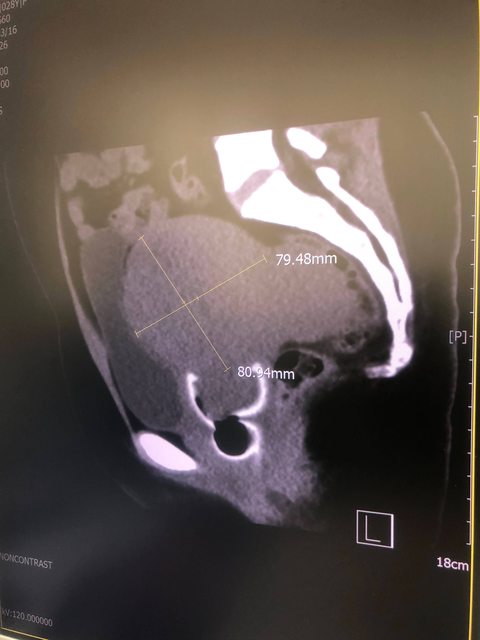

接著離開診間就是安排血檢、電腦斷層。照電腦斷層還有一個小插曲,因為還在月經期間,我正使用月釀杯,檢驗人員一直出現困惑的表情又討論很久,後來才問我:[小姐,你是有用月亮杯嗎? ];我說:[對阿,照得很清楚嗎?]:[超清楚的!!] 我們兩個對視而笑,檢驗人員有再跟醫生確認是否會影響診斷,確認沒問題後約3/19看報告順便做子宮頸抹片。

肌瘤前面那片是我的膀胱,肌瘤下方可以看的月釀杯的拉環

https://i.imgur.com/kjiwg6o.jpg

https://i.imgur.com/IiOOBzq.jpg

3/19看報告、電腦斷層情形(肌瘤已經把我的膀胱擠到扁掉)、做子宮頸抹片(後續結果為正常),當下安排4/19進行手術;4/18提早入院檢查。也跟醫生討論依我的狀況是否有傳統刀以外的選擇? 醫生表示肌瘤太大,只能開傳統刀。確認開刀時間後,請假時主管請我考量身體情形,跟醫生協調提早開刀。後來改到4/15開刀;4/14提前入院檢查,離開診間後,護理師也提供一些表單,例如病房選擇的順序,健保房、自費雙人房、自費單人房,我優先選健保房,剛好也有選到。